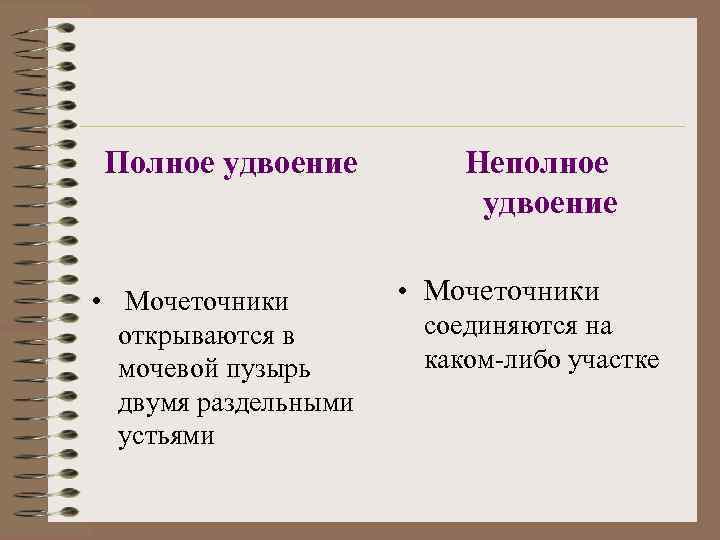

Полное удвоение • Мочеточники открываются в мочевой пузырь двумя раздельными устьями Неполное удвоение • Мочеточники соединяются на каком-либо участке